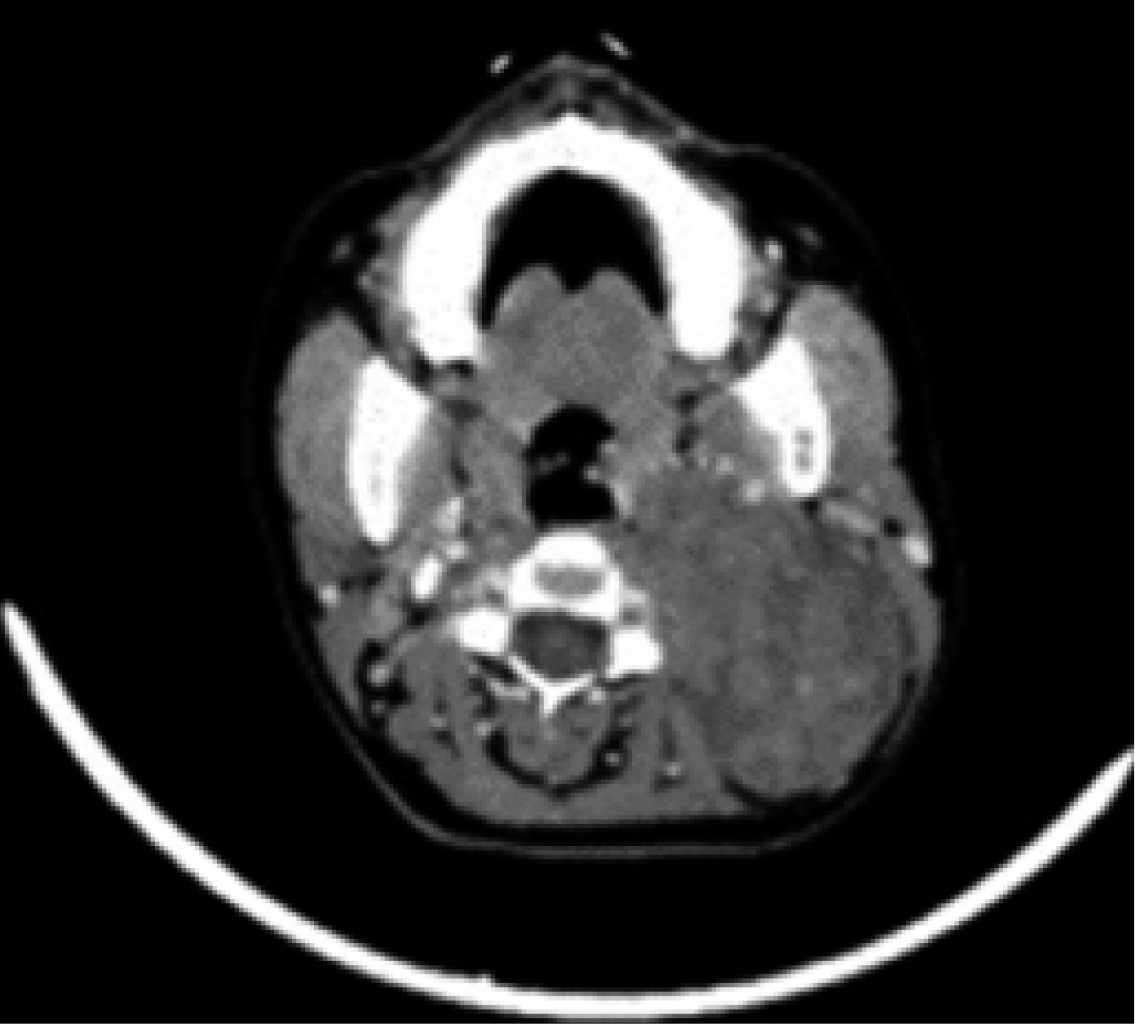

Physical examination revealed the presence of a cervical tumor measuring approximately 12 × 8 × 10 cm, indurated, and fixed to deep planes, covering regions II, III, and Va of the left hemi collar (Figure 1); it was slightly painful on palpation with a 3/10 intensity on VAS, without difficulty in opening the mouth, no facial asymmetry nor airway involvement.

There was no systemic inflammatory response syndrome, hemodynamic instability, or cardiopulmonary compromise. As a diagnostic complement, a CT scan is requested, which reports a large, rounded mass of solid appearance with regular edges, well delimited, heterogeneous, predominantly hypodense, with small areas of lower density inside, without identifying calcifications, with a density between 24 and 37 HU and that after the administration of intravenous contrast presents a density between 33 and 87 HU. It was in the left parapharyngeal level of 6.6 × 7.5 × 9.2 cm, as a left parapharyngeal space lesion with a suspected branchial cyst versus pleomorphic adenoma versus hemorrhagic branchial cyst (Figures 2, 3 and 4).